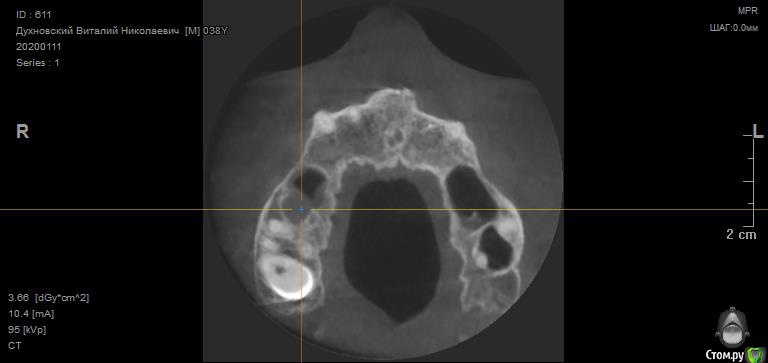

Просьба ко всем не равнодушным! Глянуть КТ верхней челюсти, 27 зуб  и место где удалили 16, может ещё где-то могут быть проблемы.  На фото видно где покраснение на дёснах, в этих местах возникают боли при движении головой. Бывает боль слева если засыпаю на левой стороне. Набуханий или флюсов нигде не видно.Прошу делиться мнениями, для меня это очень - очень важно. Стоматолог визуальных проблем на месте удалённого зуба не видит, всё зажило.

По данным КТ в зоне удалённого зуба 16 ничего особенного, разве что, ретенированный (непрорезавшийся) зуб 18.

Зуб 27 требует внимания, необходим очный осмотр.